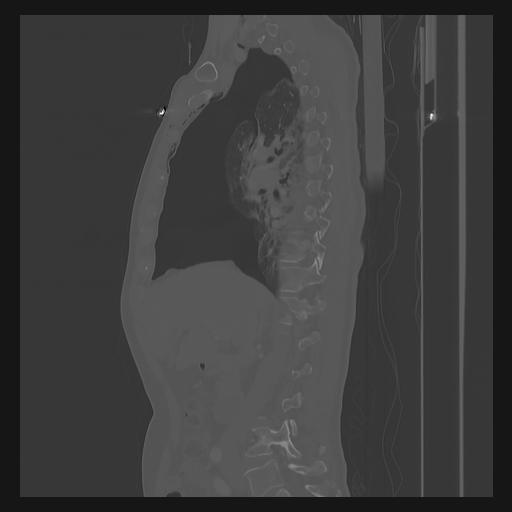

33 PULMON,CE,Sagittal,3.000,PULMON,Sagittal,